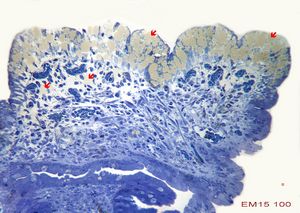

F,52y. | spirochetosis … colon (HE) … blue-stained brush border

F,52y. | spirochetosis … colon Warthin-Stary silver impregnation